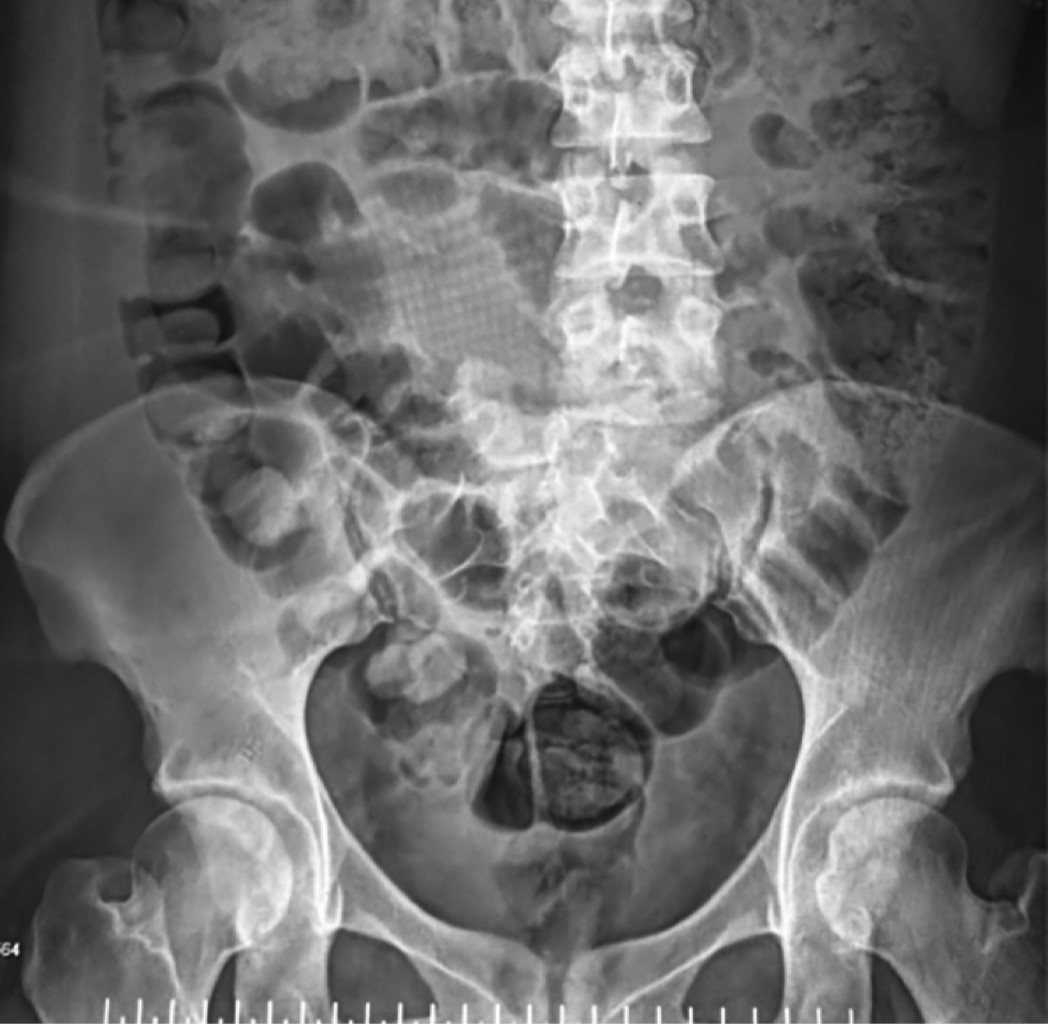

Inicia su padecimiento actual el día 5 de febrero de 2024 a las 23:00 horas al sufrir accidente vehicular como copiloto; refiere salir eyectada del vehículo al impactar contra objeto en carretera, con pérdida inmediata del estado de alerta. Atendida de manera inicial en hospital regional o por presentar trauma cerrado de abdomen que requirió laparotomía exploradora, así como hemotórax el cual se manejó con tubo endopleural. Se decide traslado a nuestro hospital de tercer nivel por presentar fractura luxación de L5-S1; ingresa a nuestro servicio el día 18/02/24. A la exploración física dirigida al ingreso se encuentra lo siguiente: extremidades superiores izquierda y derecha íntegras, con fuerza muscular valorada en escala de Daniels 5/5 en todos los grupos musculares principales y sensibilidad 2/2 en todos los dermatomos. Extremidad inferior derecha íntegra, con fuerza muscular valorada por escala de Daniel 5/5 en todos los músculos clave, sensibilidad 2/2. Extremidad inferior izquierda íntegra, con fuerza muscular valorada por escala de Daniels 5/5 en grupos musculares clave, con función motora a nivel de flexoextensión de pie y tobillo en 0/5 con dermatomo afectado L5-S1 en 1 de 2 sin poder discernir en prueba pica y toca. Se realizan estudios de imagen de manera inicial a su ingreso en unidad de politrauma, reportan lo siguiente: en radiografía anteroposterior (Rx Ap) y lateral de columna dorsolumbar se observa alteración en la congruencia articular a nivel de L5-S1 con desplazamiento en sentido coronal hacia lado derecho de columna vertebral (Figura 1). Tomografía axial computarizada (TAC) simple de pelvis en la que, en corte sagital coronal y reconstrucción 3D, se observa falta de congruencia articular a nivel de L5-S1 con traslación coronal hacia la derecha sobre el sacro, solución de continuidad ósea a nivel de 5 apófisis transversas de lado izquierdo desde L1 a L5 (Figuras 2 y 3). Se decide ingreso a cargo del Servicio de Ortopedia con diagnóstico de fractura luxación L5-S1 AO 53C TLICS 8 puntos Asia B.